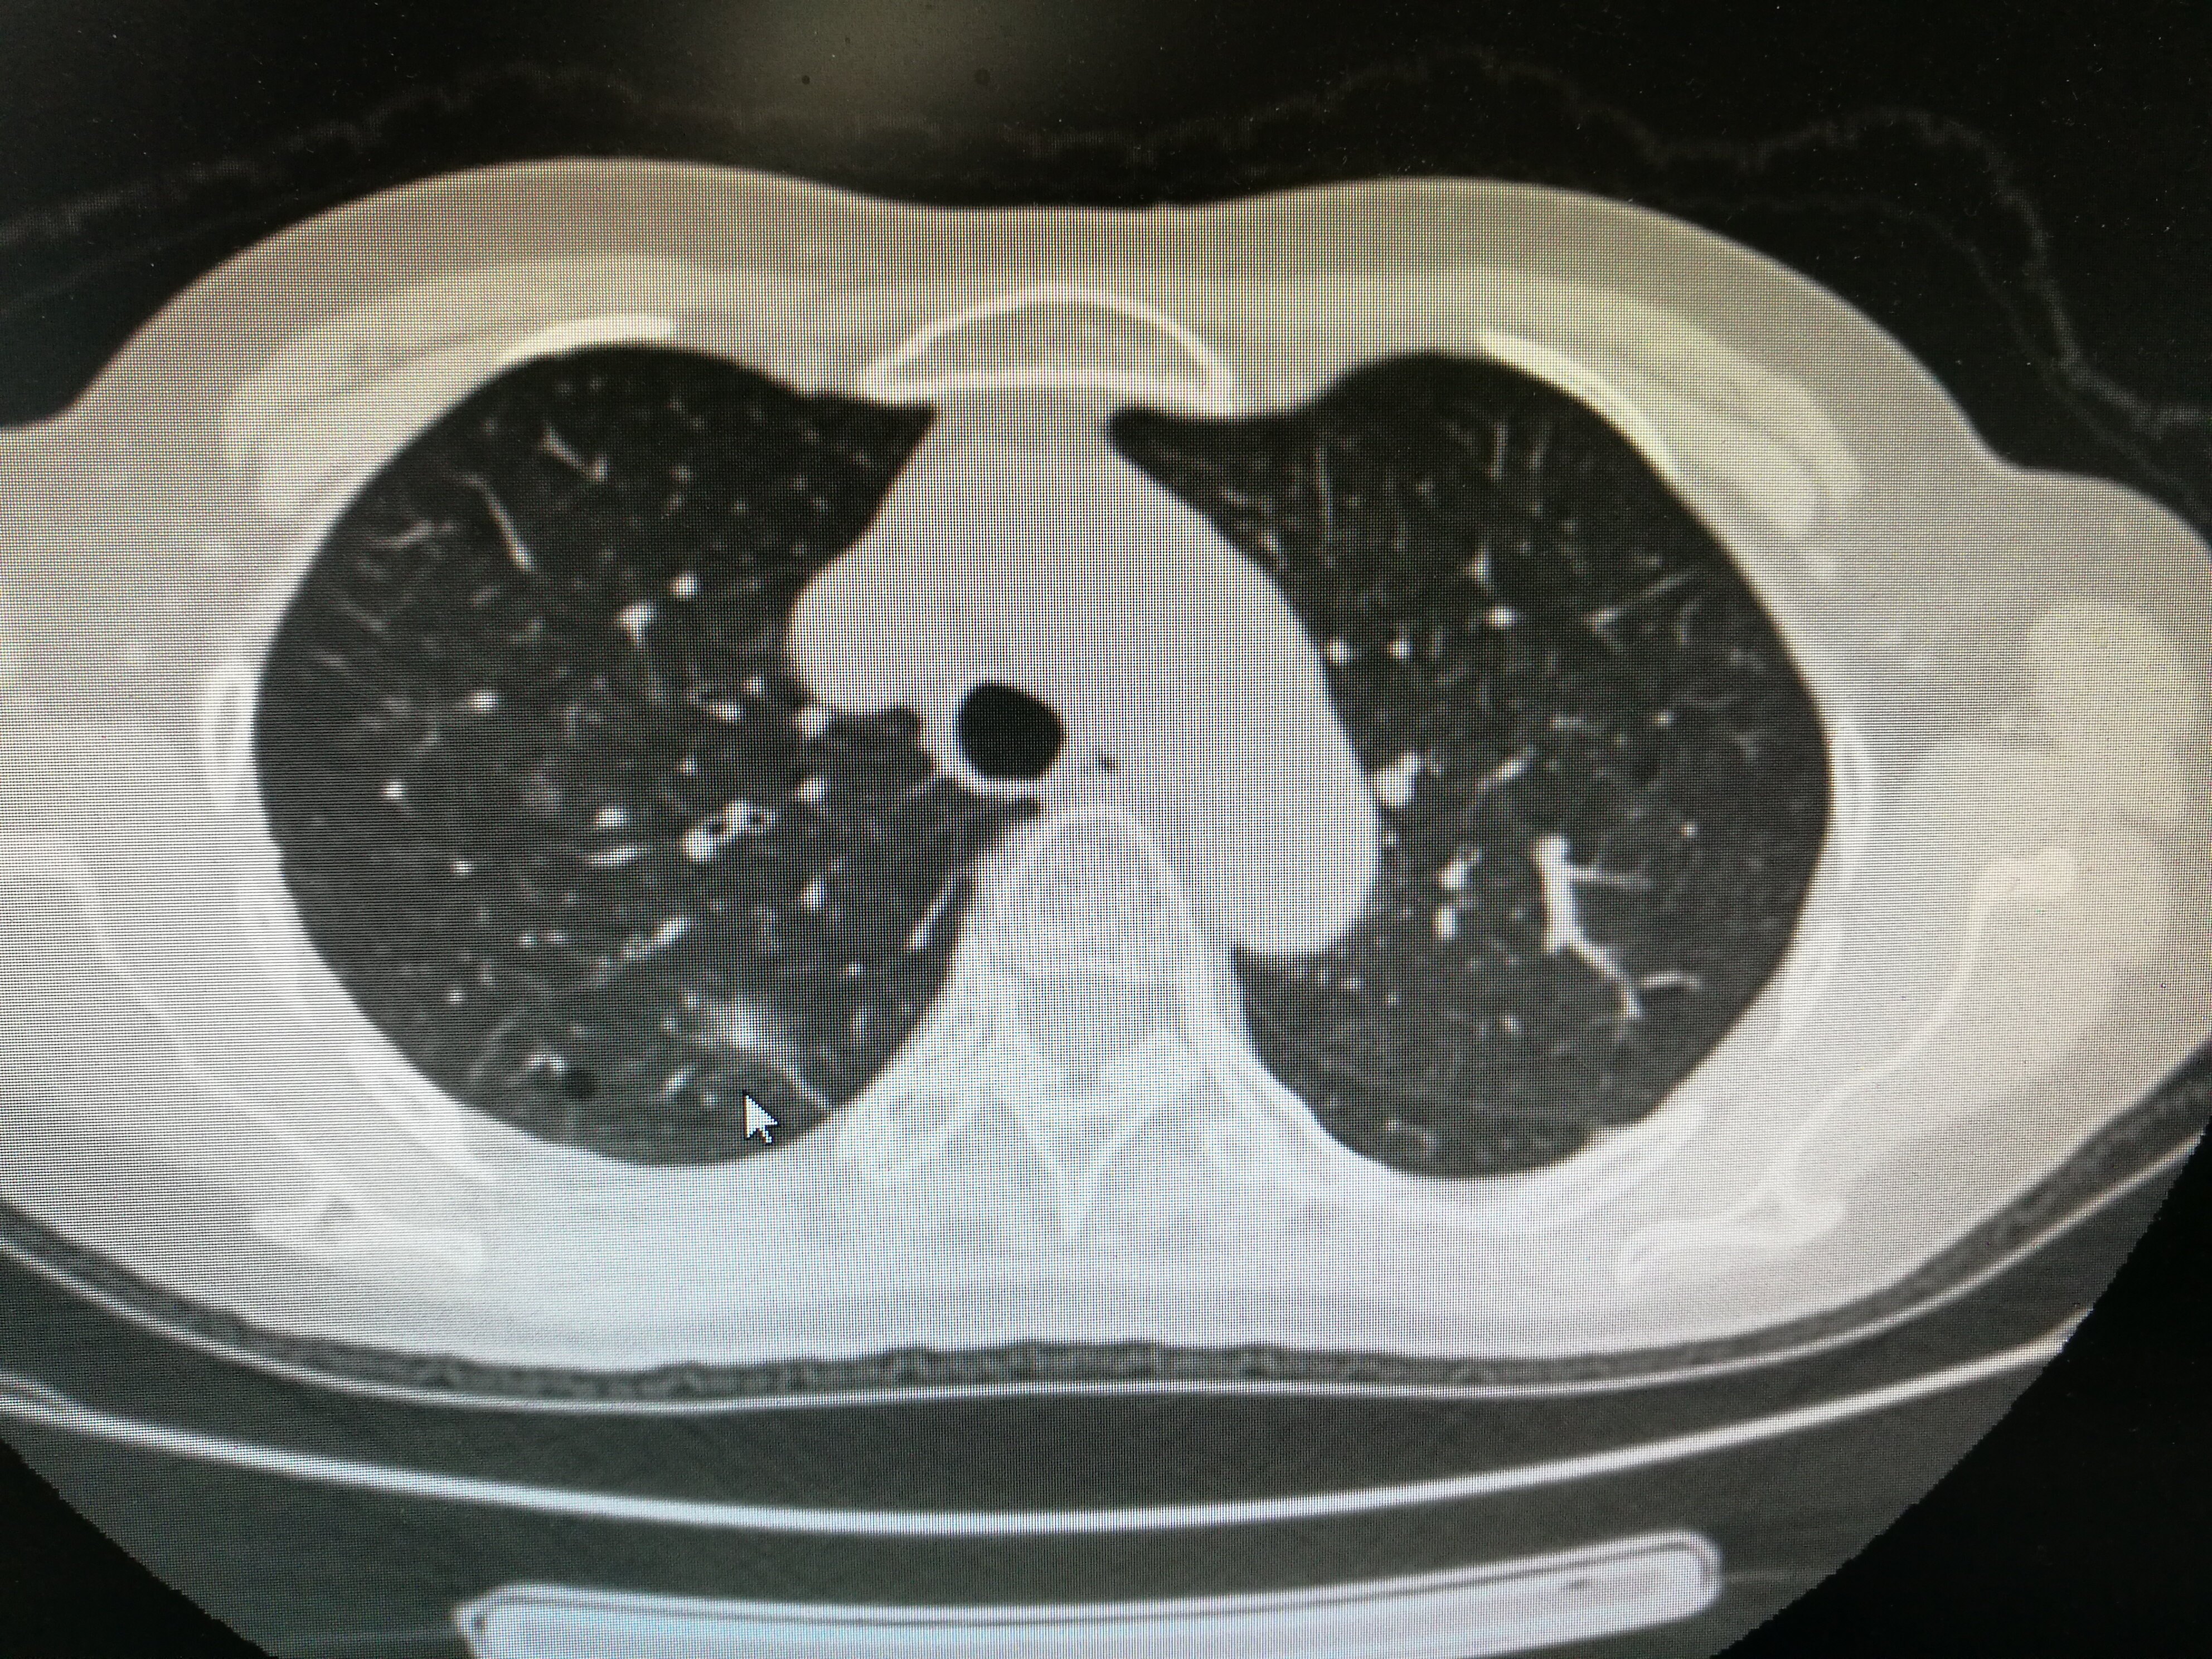

在5年曾经,人们做健康复检还基本都是用普通的拍片,因为拍片发现不了大于一cm的肿瘤,非常是磨玻璃样的肿瘤肺结节最怕三种运动较真,愈发是很难发现,因而,那种时侯测量的小结节特别少。但近来几年,随着CT越做越多,越来越多的小结节被找了下来。

从40岁开始做CT筛查。不推荐40岁以下常规做脑部CT。最有效的手段还是低剂量的螺旋CT,幅射小,对小结节的发觉率是93%。